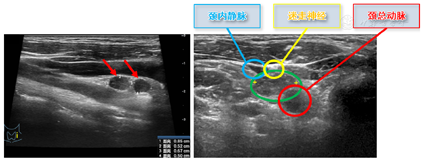

2021年1月20日我院复查超声可见:甲状腺全切术后,右侧颈部Ⅲ区见数处低回声区,大小分别约22 mm×5 mm(内可见局部无回声及结节状高回声,内可见点状强回声)、9 mm×3 mm(颈内动脉外侧)、10 mm×4 mm(颈总动脉前方),右侧颈部V区可见一个混合回声,大小约18 mm×10 mm,左侧颈部Ⅵ区见一处低回声区,大小约10 mm×3 mm,左侧颈部Ⅲ区可见一个低回声,大小约4mm×3mm(颈内静脉外侧)(以上淋巴结超声图像见图1)。左侧颈部Ⅳ见两处低回声区,大小分别约8 mm×5 mm、7 mm×5 mm(颈总动脉与颈内动脉之间,毗邻迷走神经,见图2)。各淋巴结形态尚规则,淋巴门回声消失,CDFI示其内可见点状血流信号。超声提示:甲状腺全切术后,双侧颈部淋巴结肿大伴结构异常,考虑MT。